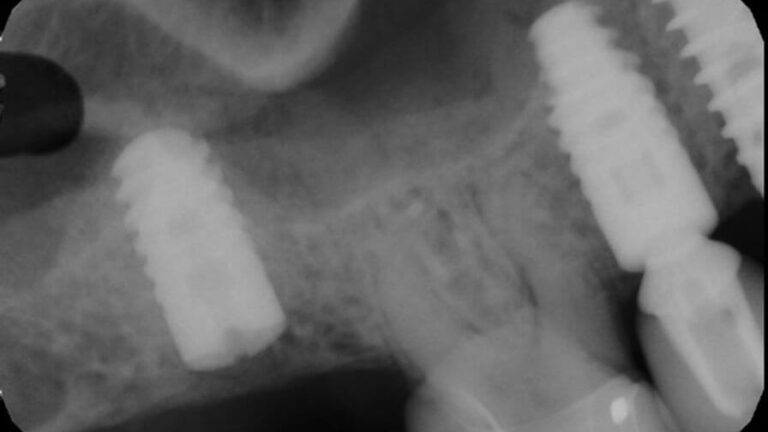

Ankylos Fractured Abutment (Non-indexed, pre-C/X) in #2 site – 0013

The patient presented on referral from his general dentist with a fractured Ankylos abutment in the #2 site.